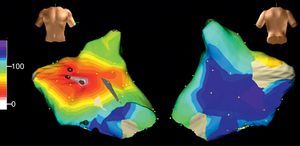

Taquicardia macrorreentrante auricular izquierdaLa estructura anatómica de la AI no contiene los grandes obstáculos de la AD, y quizá por eso las TAMR de la AI han sido poco frecuentes. En pacientes sin antecedentes de cirugía la TAMR de AI se produce en presencia de amplias áreas inexcitables de bajo voltaje y áreas de bloqueo de conducción que forman el núcleo central del circuito, ya sea por sí mismas, ya sea por su anexión a algún obstáculo anatómico (orificios de las venas pulmonares u orejuela) (Figura 12, Figura 13)17, 26, 27. La TAMR de AI se asocia a cardiopatías orgánicas (miocardiopatías, valvulopatías) y a patrones de grave trastorno de conducción interauricular (bloqueo del haz de Bachmann)28. Un sustrato frecuente de la TAMR de AI son las atriotomías quirúrgicas de cirugía valvular mitral29 o de cirugía de fibrilación auricular30. En los últimos años, el gran auge de la ablación de la fibrilación auricular, con destrucción de amplias zonas de miocardio auricular, ha dado pie a una alta incidencia de TAMR de la AI en estos pacientes31, 32, 33, que lleva a la necesidad de nuevos procedimientos de ablación en un buen número de ellos.

Figura 12. A: cartografía electroanatómica (Navx®) en visión anterior, de un circuito de taquicardia auricular macrorreentrante en torno al anillo mitral en paciente sin antecedentes quirúrgicos; obsérvese la amplia zona inexcitable de bajo voltaje (en gris) en la aurícula izquierda posterosuperior. B: cartografía en visión oblicua anterior derecha de una taquicardia auricular focal muy lenta (ciclo, 430 ms) inducible tras la interrupción de la taquicardia auricular macrorreentrante con aplicaciones de radiofrecuencia entre la zona de bajo voltaje y el anillo mitral (puntos rojos); esta taquicardia auricular focal se origina en la vena pulmonar superior derecha (área blanca); como en el caso de la figura 6, una línea de bloqueo obliga al giro del frente de activación que termina al otro lado de esta zona de bloqueo (azul-violeta). BV: bajo voltaje; LC: longitud del ciclo.

Figura 13. Cartografía electroanatómica (Navx®) en visión anterior (A) y posterolateral derecha (B) de una taquicardia auricular macrorreentrante girando en torno a la vena pulmonar superior derecha. Obsévense las zonas inexcitables de bajo voltaje, especialmente en la aurícula izquierda posterior.